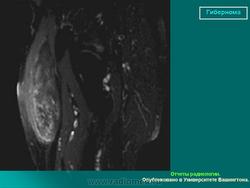

Гибернома (син.: бурая липома, липома из липобластов, мультилокулярная липома) — редкая доброкачественная опухоль, гистогенетически связанная с элементами бурого жира.

Гиберномы локализуются в определенных местах — на спине (в межлопаточной области), на боковой поверхности шеи. в подмышечных ямках, паховых областях, подколенных ямках. Их локализация совпадает с местом расположения бурого жира. Возраст больных чаще молодой — до 30 лет. Пол значения не имеет.

По клиническому течению гибернома это медленно растущие доброкачественные опухоли. Новообразования четко контурированы, безболезненны.

Макроскопический вид гиберномы достаточно характерен благодаря желтовато-бурой или охряно-желтой окраске. Узлы мягкие, с выраженной дольчатостью, достигают размеров 4-8 см.

Гибернома (hibernus - зимний) - редкая форма опухоли жировой ткани.По внешнему виду напоминает бурый жир животных, впадающих в зимнюю спячку. Встречается как доброкачественный, так и морфологически злокачественный вариант опухоли с характерной локализацией в межмышечных прослойках подмышечной области, шеи, межлопаточной области. Может локализоваться в средостении, редко на конечностях. Возникает у людей молодого или среднего возраста. Клинические симптомы те же, что и при липомах. Имеет характерные гистологические отличия от липомы, но во многом и сходна по строению с ней.